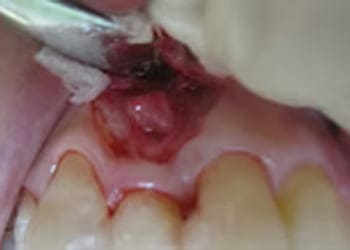

親知らずの治療は、基本的に抜歯が適応となります。

しかし、埋まった状態の親知らずの抜歯は難易度が高く、特に下顎の親知らずは顎の骨の中にある知覚神経(触覚や痛覚をつかさどる神経)や血管に近接しているため、抜歯後に唇や顔面皮膚の知覚異常が生じたり、抜歯部位から大量に出血したりする可能性があります。

もちろん、正常に萌出してきちんと噛めているものや、今後正常に萌出する可能性があるものについては、必ずしも抜歯する必要はありません。